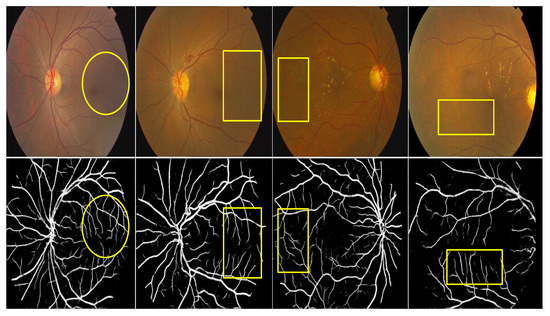

3.3. Qualitative Analysis